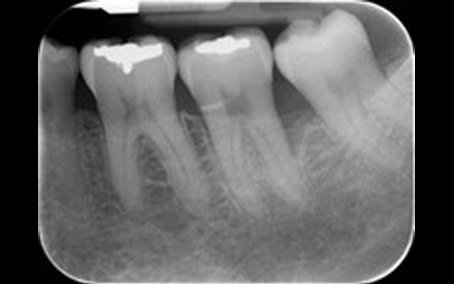

Dr Rupal Patel – Specialist Periodontist

Radiograph 1 2018

Radiograph 1 2023

Radiograph 2 2018

Radiograph 2 2023